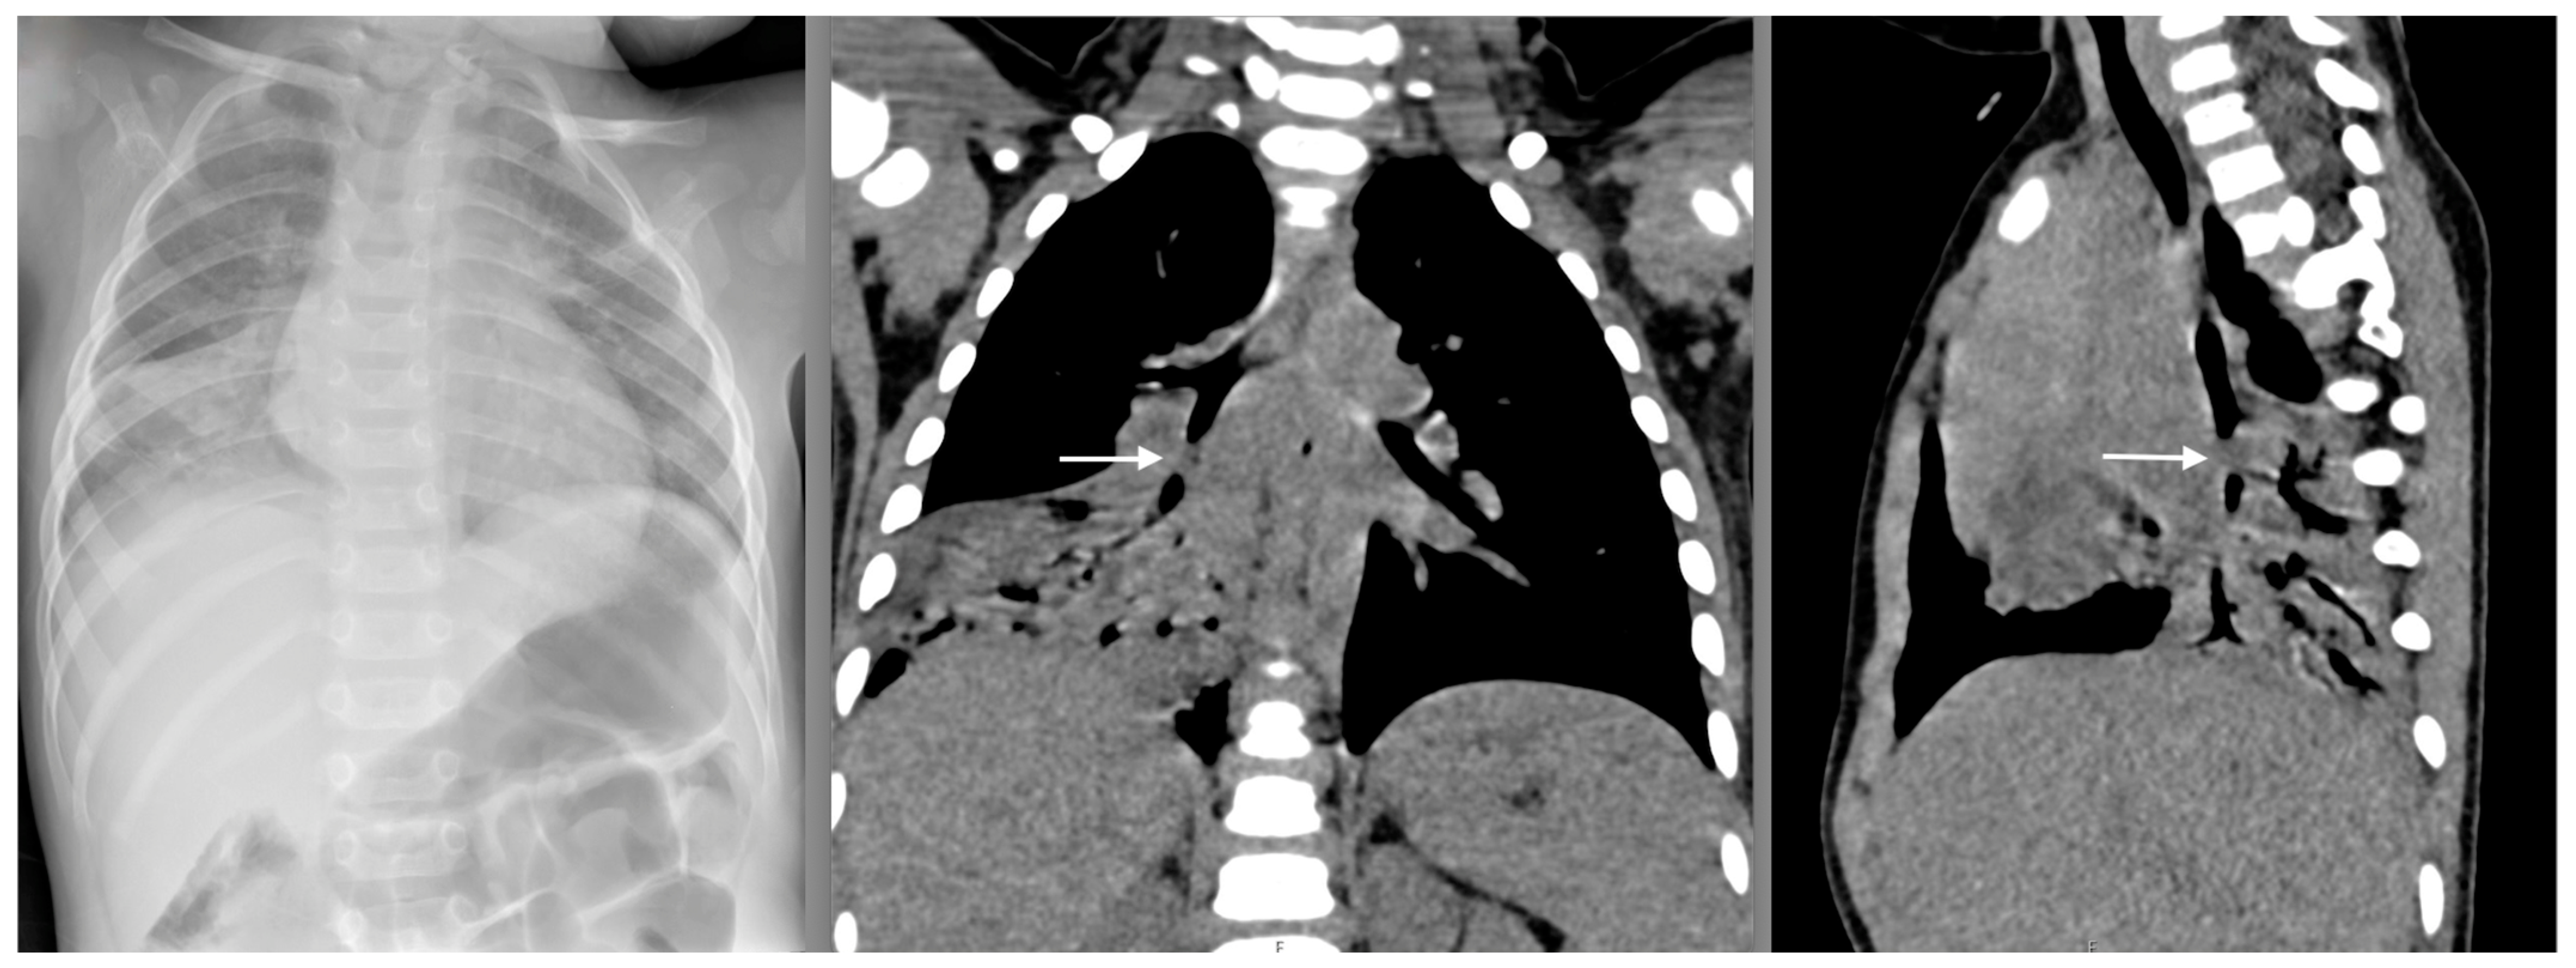

6. Tracheobronchial Foreign Bodies